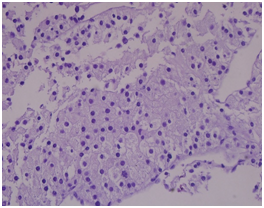

CT scan guided liver biopsy was done and reported as Metastatic carcinoma, morphologically and immunohistochemically goes with adrenal gland cortical origin (adrenal cortical carcinoma) (Figure 5).

Figure 5 H & E Staining: Shows malignant cells.

Immuno-histochemical studies of the tumor was as follows: Melan A: Positive (Figure 6), Alpha inhibin: Positive (Figure 7), Calretinin: Negative, Chromogranin: Negative, Renal cell carcinoma (RCC): Negative, Hep Par 1: Negative hence confirming the diagnosis of adrenal cortical carcinoma.